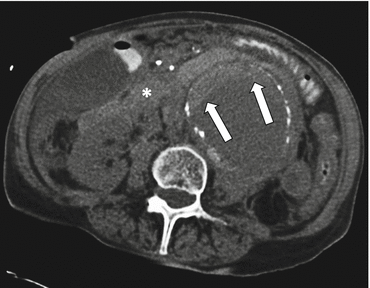

Fig. 7.2

Hyperattenuating crescent sign. Transaxial noncontrast CT image shows an infrarenal aortic aneurysm with a crescent-shaped area of high attenuation in the mural thrombus (arrows), representing acute hematoma. There is also rupture, evidenced by surrounding retroperitoneal hematoma (*)